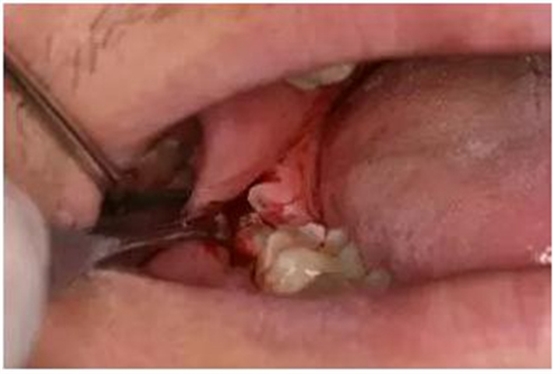

圖3.患者口內(nèi)觀:48僅萌出頰側(cè)近中一牙尖,遠(yuǎn)中有牙齦覆蓋

圖7.順著牙列長(zhǎng)軸方向、略偏頰側(cè)切開(kāi)遠(yuǎn)中齦瓣,長(zhǎng)度約1cm為宜